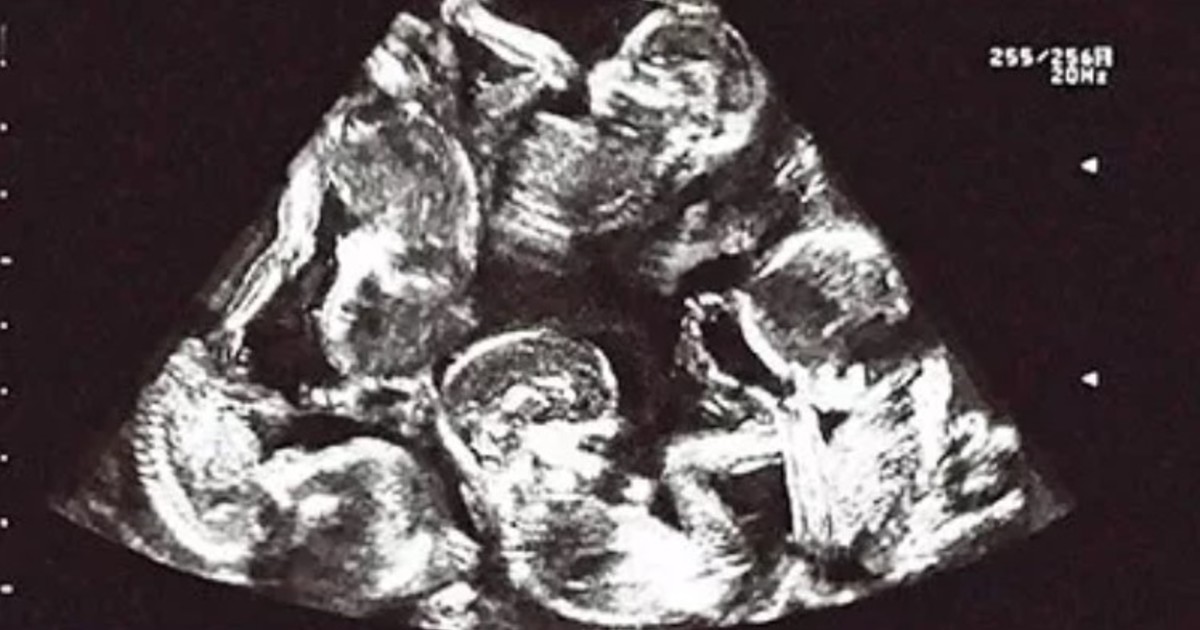

• El origen de esta gestación múltiple, de acuerdo con los médicos, estaría en el consumo de medicamentos para la infertilidad sin control médico.

• Todavía está por decidirse si la mujer dará a luz a los nueve bebés.